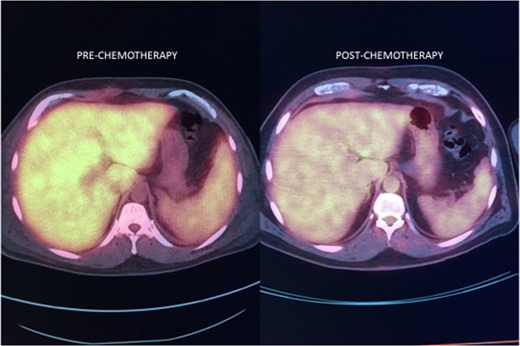

Noncutaneous IVLBCL in particular is normally associated with poor long-term prognosis. In most cases, IVLBCL is disseminated at the time of diagnosis, warranting treatment with systemic therapy [1]. Successful IVLBCL treatment has been achieved with modified R-VNCOP-B (etoposide, mitoxantrone, cyclophosphamide, vincristine, prednisolone and bleomycin plus rituximab) regimen [2]. R-CHOP therapy, utilized in combination with high-dose methotrexate therapy as prophylactic CNS coverage, has also been successful in other IVLBCL cases with hepatic involvement [3, 7].

There is only one other case report in the literature describing IVLBCL isolated to the liver and the patient had a similar constellation of symptoms to ours [7]. Most reports of IVLBCL cases share similar presentations: prolonged fevers, elevated liver enzyme levels, hyperbilirubinemia and elevated LDH levels [8, 9]. A reported severe variant of IVLBCL includes multiorgan failure, pancytopenia and hemophagocytic syndrome [10, 11]. As outlined in our report, elevated liver function tests, leukocytosis and fevers caused significant concern for post-operative complications after a routine gallbladder surgery. In the end, the findings were all due to an underlying pathology unrelated to surgical gallbladder disease.